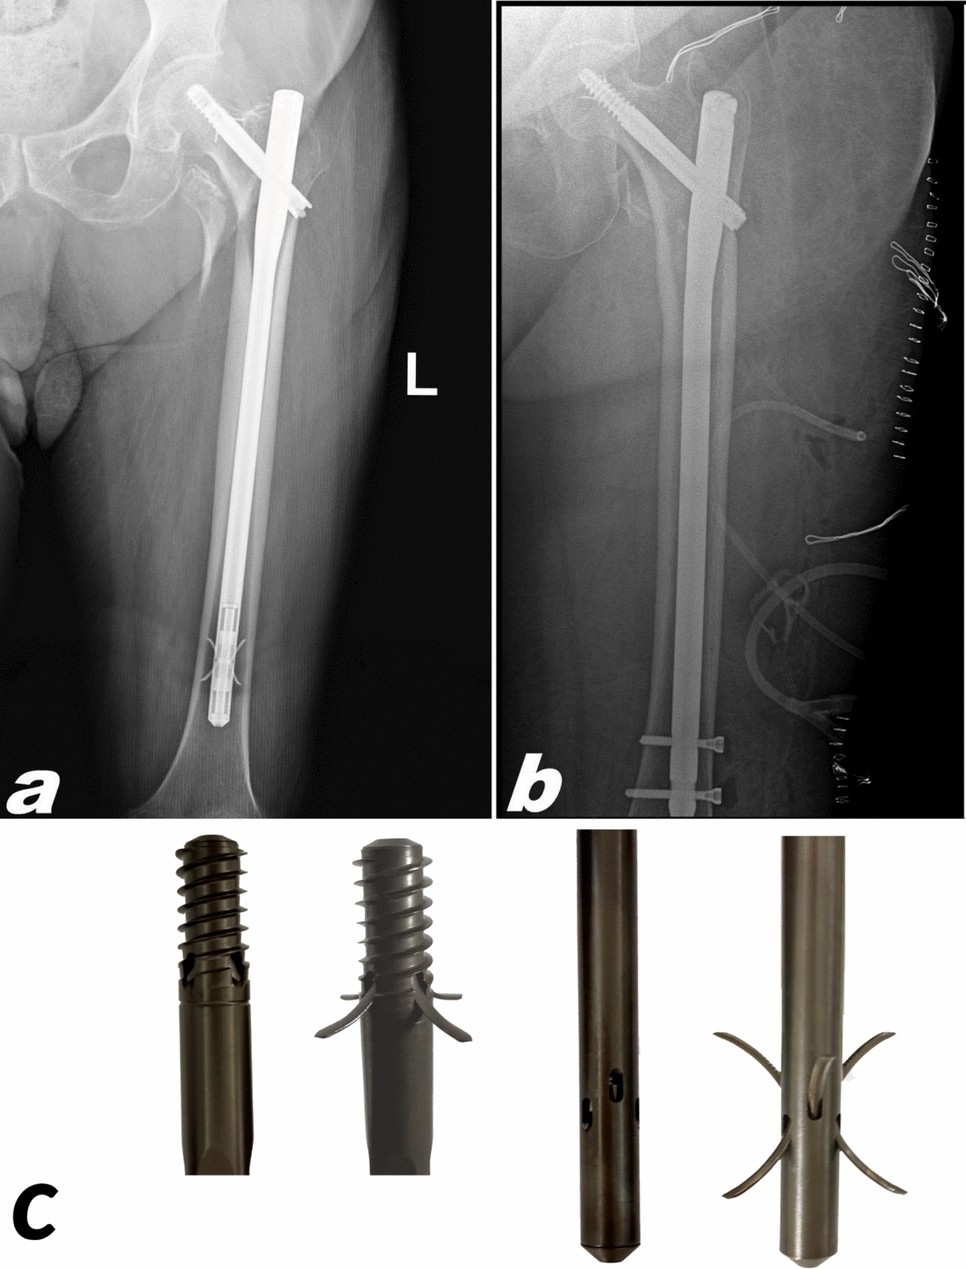

» Long gamma nail (97) 사진

Long gamma nail (97) 사진